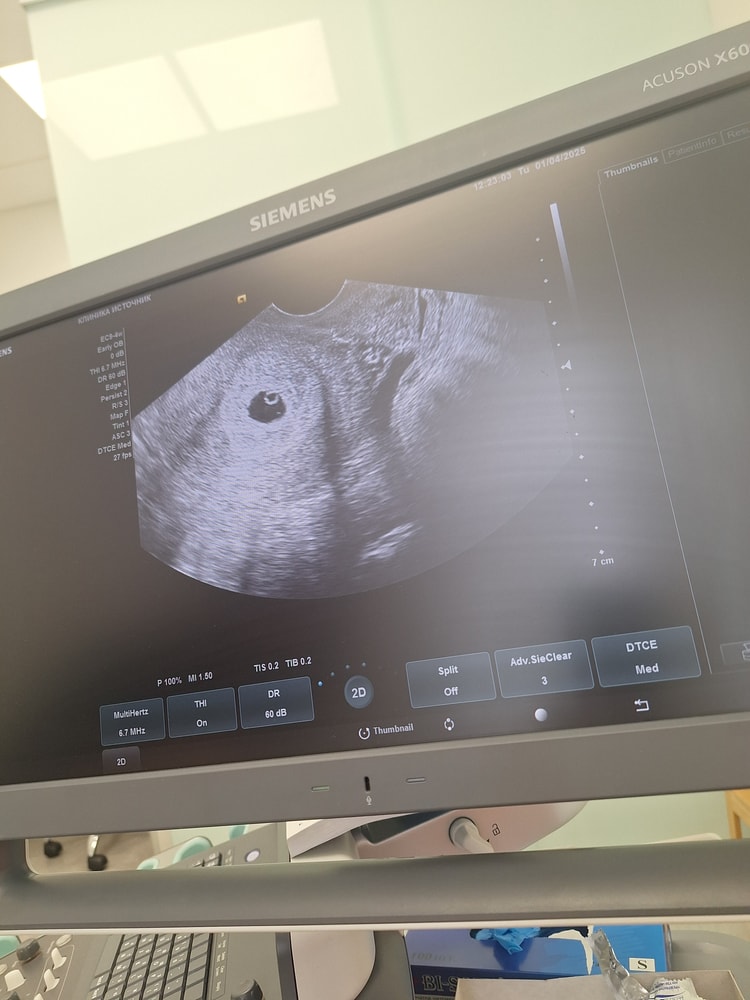

Оленька в ЭКО-мама 8 месяцев Узи и 20дпп Всё о нашей беременности На Узи увидели плодное яйцо 12.1мм и ж.м Следующее узи 9апр Посмотрите еще 20 записей на эту тему Лучший ответ Счастливая мама Тихонечко поздравляю! Благополучно беременности! 🤞 01.04.2025 Ответить Отменить Ответить случится чудо Поздравляю 🎉 какая у вас динамика ХГЧ? 01.04.2025 Ответить Оленька случится чудо, 7дпп-34 9-90 11-233 13-680 17-4500 Вот такое хгч 01.04.2025 Ответить Таня Здравствуйте, где делали? 01.04.2025 Ответить Оленька Таня, Евромед Инвитро 01.04.2025 Ответить Лия Поздравляю ! Вы по какому фактору шли ? И какая стимуляция была ? 01.04.2025 Ответить Оленька Лия, мужской фактор,гоналом стимуляция 01.04.2025 Ответить Крио перенос один эмбрион, у кого так же было? Как успокоиться?!😅 Чаты Беременных Выберите чат: Январята-2026 Февралята-2026 Мартята-2026 Апрелята-2026 Майчата-2026 Июнята-2026 Июлята-2026 Августята-2026